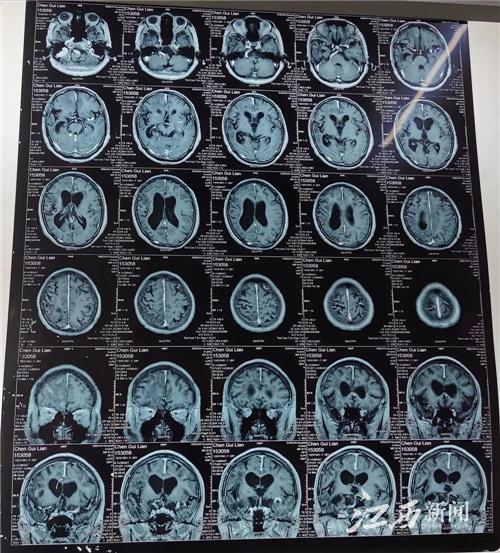

圖為2020年術前頭顱磁共振片

接診的徐春華聽了癥狀描述后,立刻安排她做了進一步磁共振檢查和腦電圖檢查,發現顱內右側額葉有多個明顯的寄生蟲肉芽腫病灶,癲癇放電也來自右側前頭部。

徐春華介紹,大腦受到散在多發的寄生蟲病灶刺激和破壞,是引起癲癇發作的主要原因。